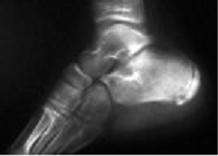

En las talalgias de crecimiento, que afectan a niños de 8 a 10 años, puede doler el talón, pero a los lados. Clásicamente se incluían dentro de la osteocondritis isquémica aséptica o enfermedad de Sever (figura 2), pues radiográficamente se aprecia una condensación ósea en forma de media luna, semejante a un foco de necrosis.

Sin embargo, hoy se sabe que la imagen radiográfica corresponde al núcleo de osificación de la tuberosidad, que aparece a esa edad y desaparece hacia los 12-14 años tras osificarse completamente. El dolor real proviene del punto de inserción de la aponeurosis y del tendón de Aquiles, debido a un proceso de osteotendinitis.

Figura 2. Enfermedad de Sever